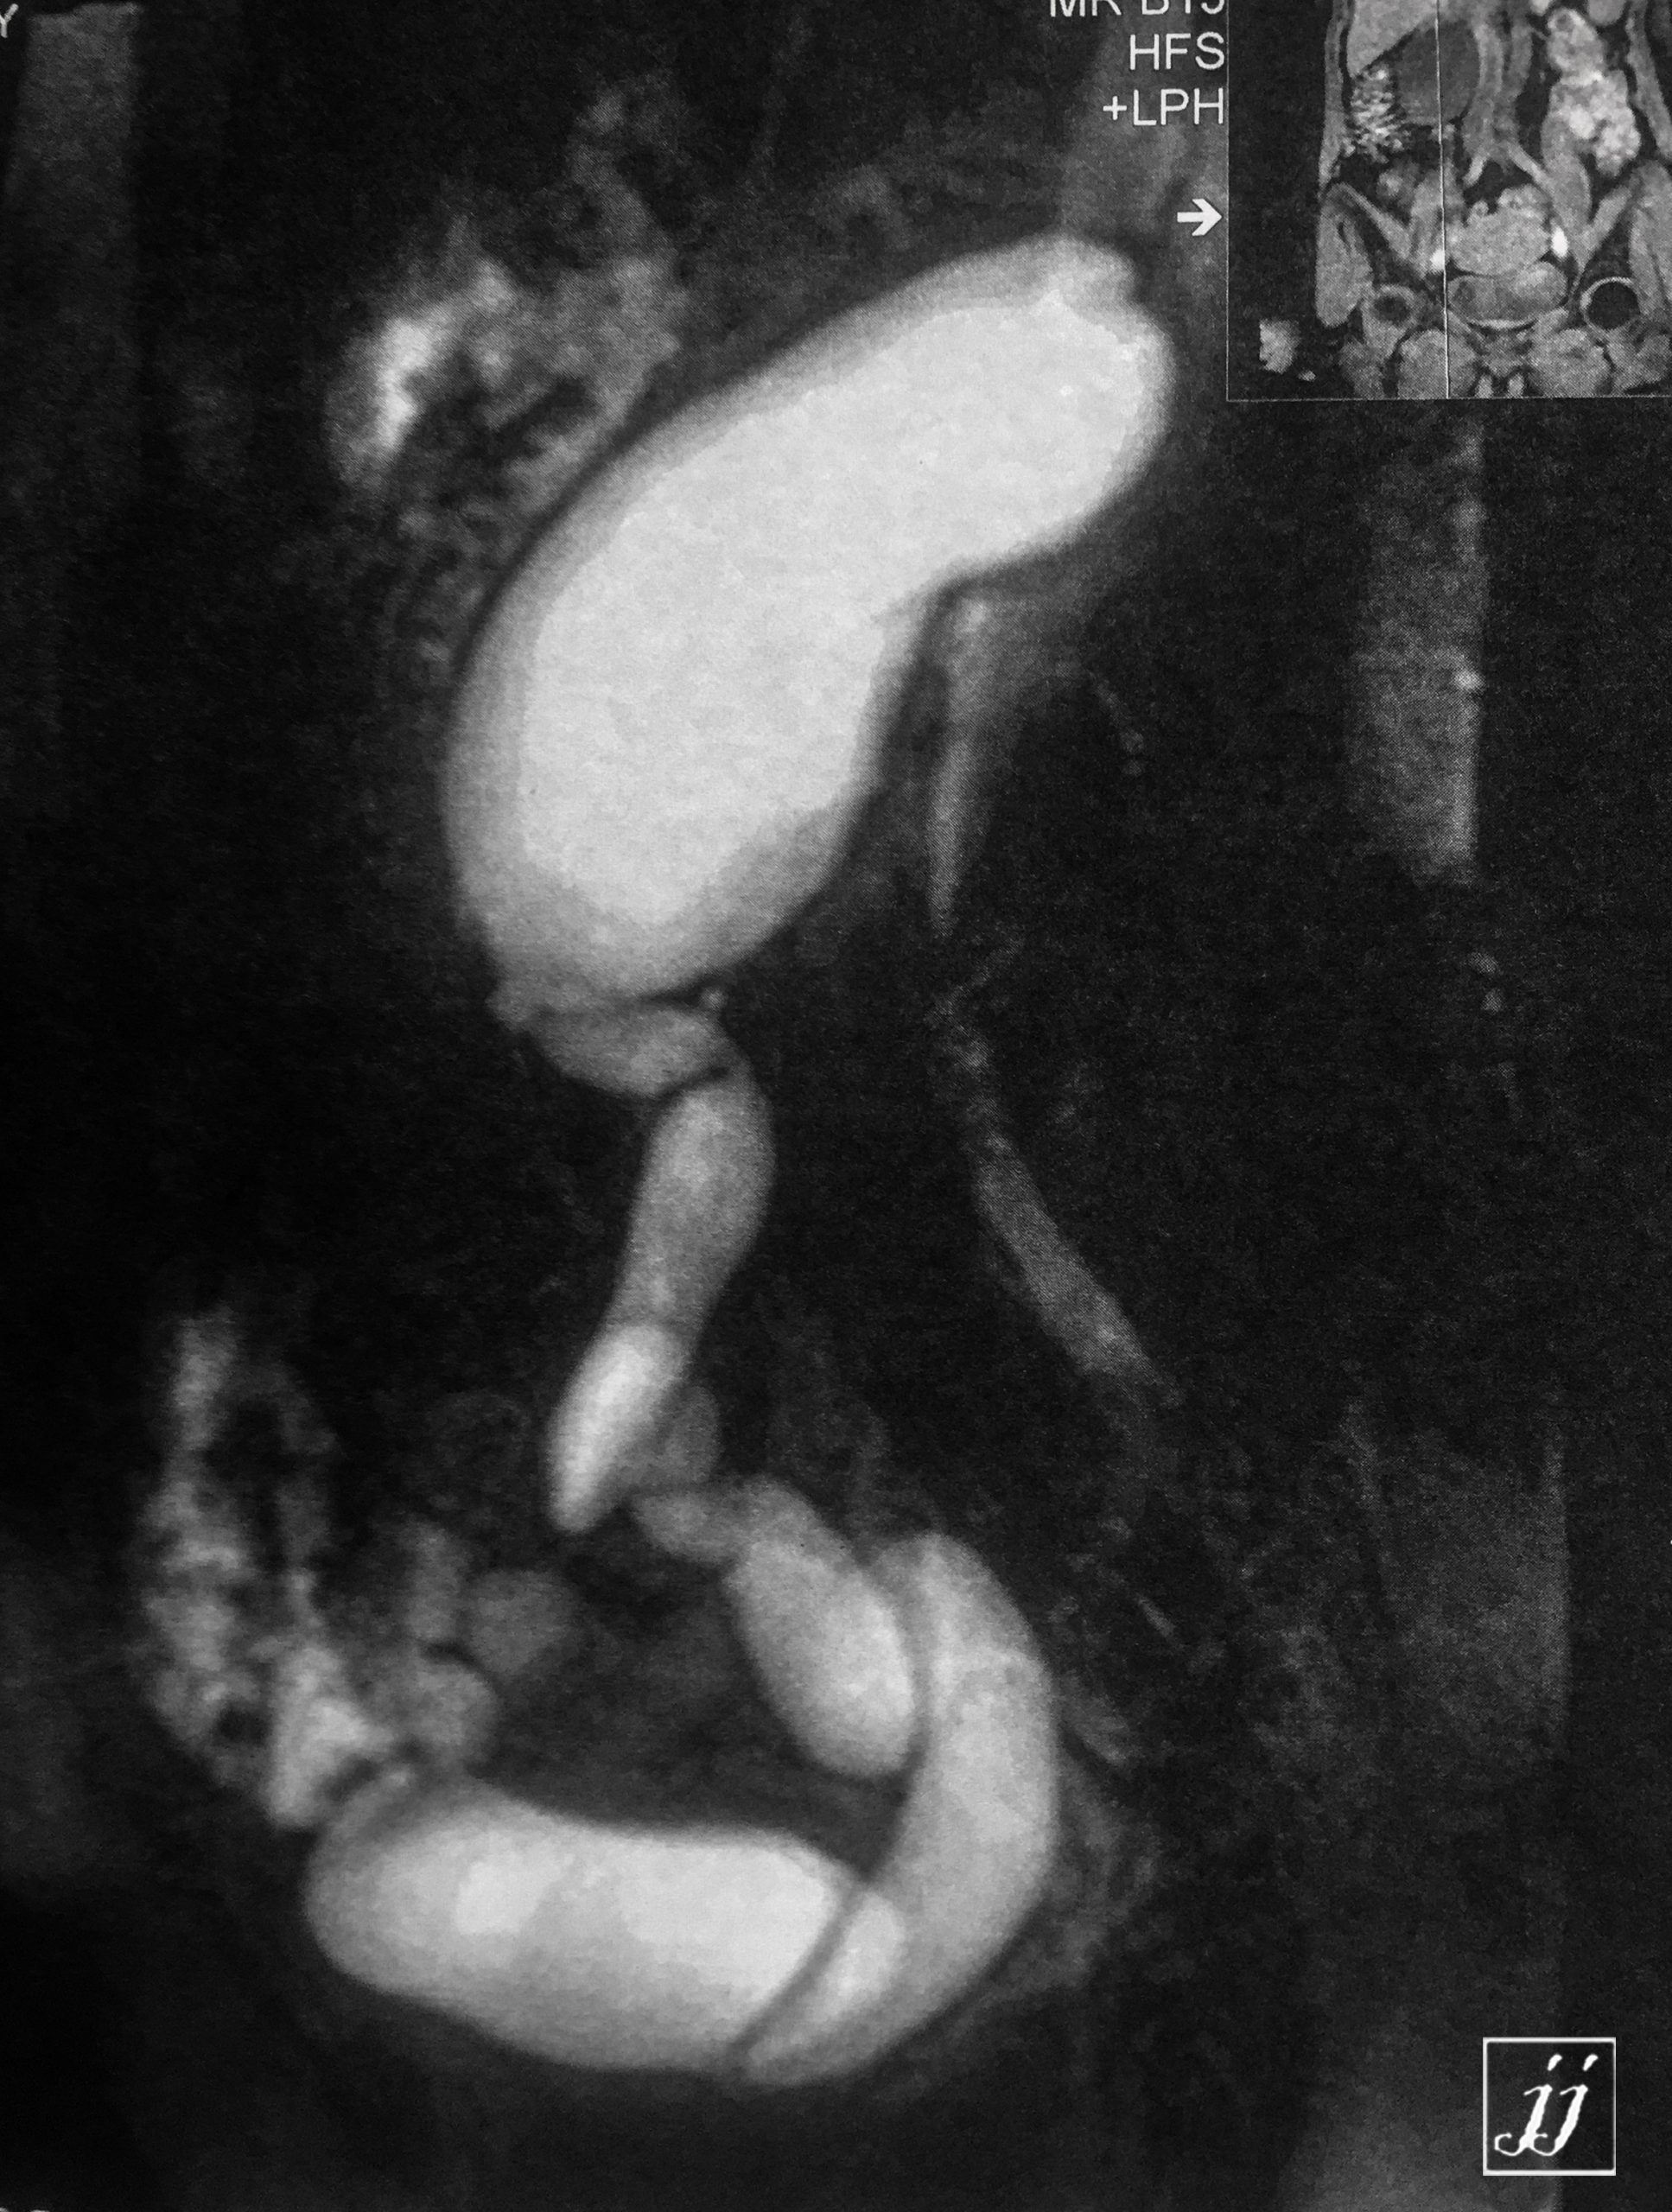

Abdomen- right side severe hydronephrosis and ureter (6)